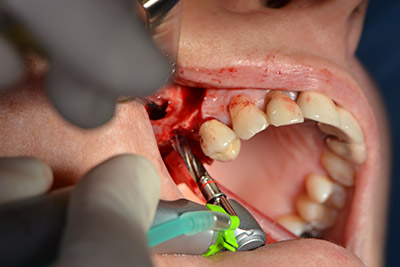

Dunque, l'impianto viene posizionato e l'osso ricostruito. In questo caso, considerate le dimensioni della regione di accrescimento, i microframmenti dell'osso autologo (raccolti con un'apposita cannula di aspirazione in seguito alla perforazione dell'impianto 16 e della fenestrazione 14) vengono combinati con dei materiali di riempimento dell'osso.

Una membrana riassorbibile viene usata come barriera in direzione buccale per contenere l'accrescimento. Infine, vengono applicate suture resistenti alla saliva (da fig. 15 a 19).

Accrescimento con osso autologo

Impianto

Implantologia

sutura della ferita a prova di saliva